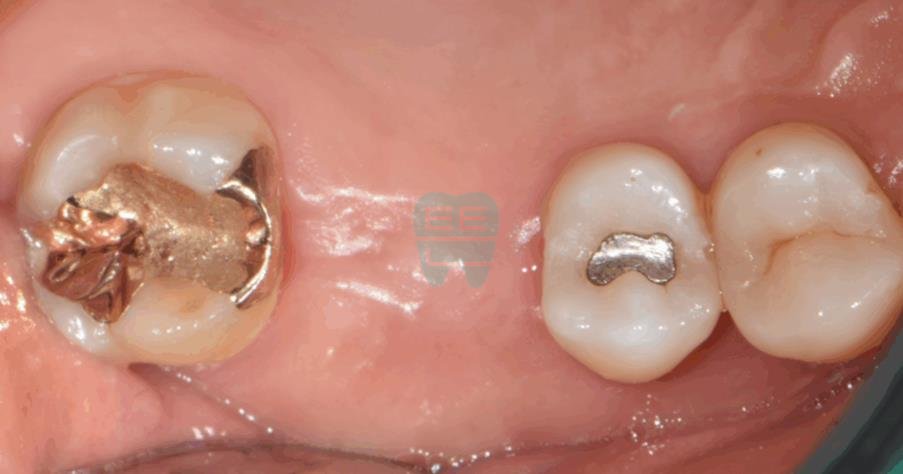

**Initial Intraoral Photo** — The patient presented with a missing tooth requiring implant treatment.

**Post-operative Intraoral Photo** — Clean surgical site with no incision.

**Final Prosthesis Intraoral Photo**

Pre-operative intraoral photo showing the missing tooth site